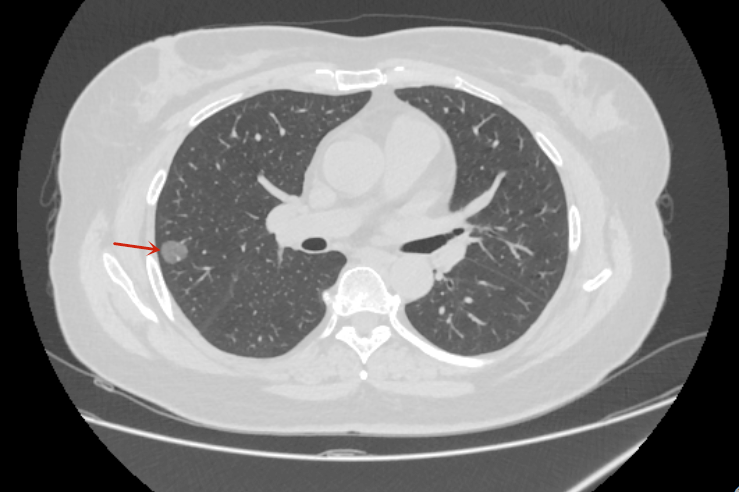

患者张女士在体检中发现右上肺多发结节结节,最大直径约1.2cm,经影像学评估后,医生建议行右上肺叶切除术。术后病理确诊为微小浸润性肺腺癌,属于早期肺癌。目前患者恢复良好,术后无需接受化疗,仅需定期复查。

▲胸部CT是右上肺、右中肺多发肺结节(箭头所示)